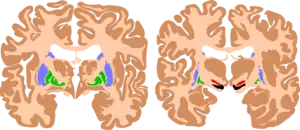

![]() | |

| The basal ganglia are instrumental in motor function. Damage to these areas may results in athetoid/ dyskinetic cerebral palsy (ADCP), or subtle movement disorders. | |